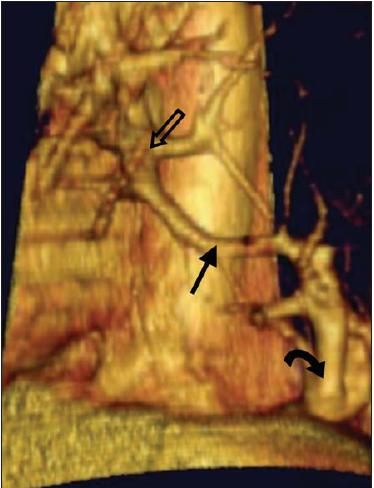

Figure 3 – This left lateral view of a 3-dimensional reconstruction of the CT scan of the chest shows the direct connection (straight solid arrow) between the aberrant artery (curved arrow) and the left pulmonary vein (hollow arrow).